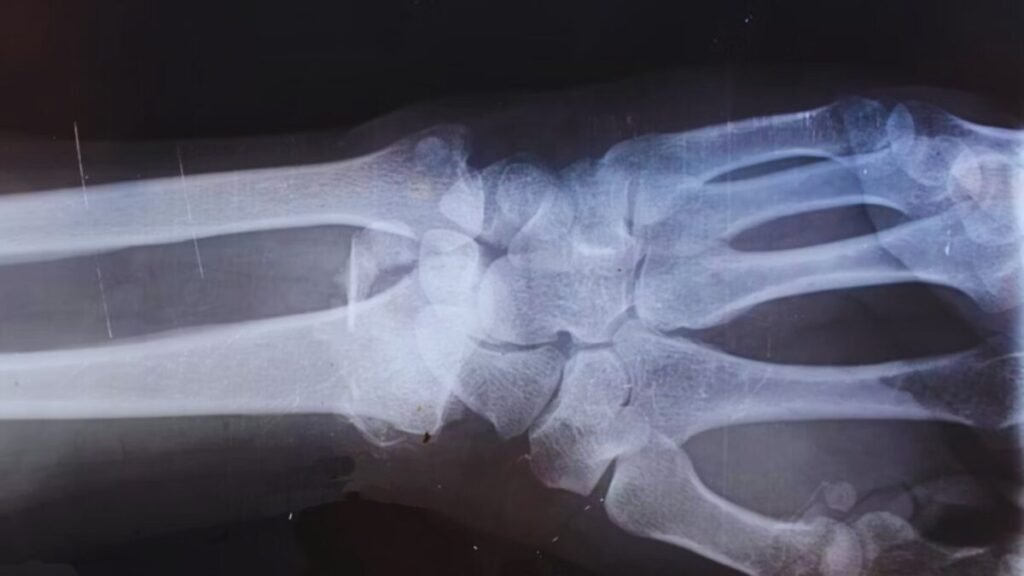

Muscle Cells as Bone Repairers

Prg4+ stem cells found in skeletal muscle have been identified as crucial for bone healing, transforming into essential bone-regenerating cells at the fracture site.